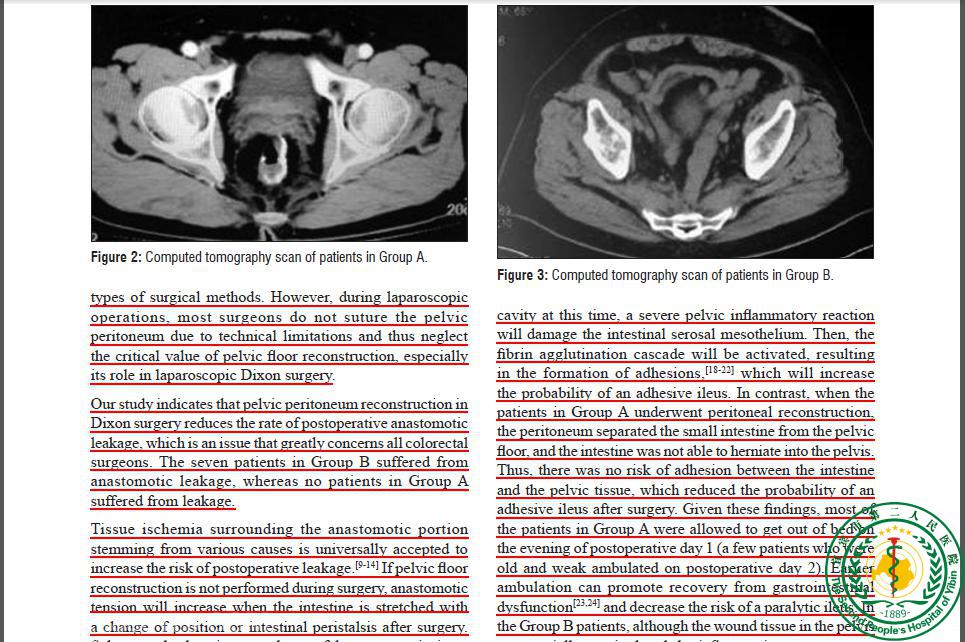

Clinical Significance of Pelvic Peritonization in Laparoscopic Dixon Surgery26282